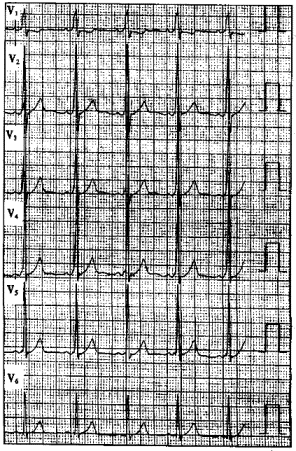

患者女性,28岁,有心悸史。平时心电图如下图所示。

11.行食管心房调搏检查,诱发出心动过速如下图所示(图中ES()为食管导联心电图),应诊断为

正确答案:10.C;11.C 解题思路:心电图显示窦性心律,间歇性预激图形:PR间期由0.16s缩短为0.10s,QRS波群时限由0.08s增宽到0.13s,QRS波群起始部有delta波。如下图为心动过速发作时心电图,心室率约为170次/分,RR间距绝对规则,RP′间期<P′R间期,食管导联RP′间期为110ms,V导联RpI间期为150ms,显示左心房激动早于右心房激动,应诊断为顺向型房室折返性心动过速(左侧旁路)。